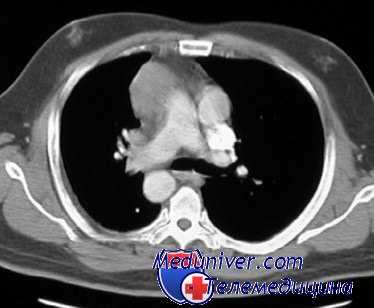

В основе развития травматического шока лежит массивная кровопотеря, выраженный болевой синдром, нарушение функции жизненно важных органов и психический стресс, обусловленный острой травмой. При этом потеря крови играет ведущую роль, а влияние остальных факторов может существенно различаться. Так, при повреждении чувствительных зон (промежности и шеи) возрастает влияние болевого фактора, а при травме грудной клетки состояние больного усугубляется нарушением функции дыхания и обеспечения организма кислородом.